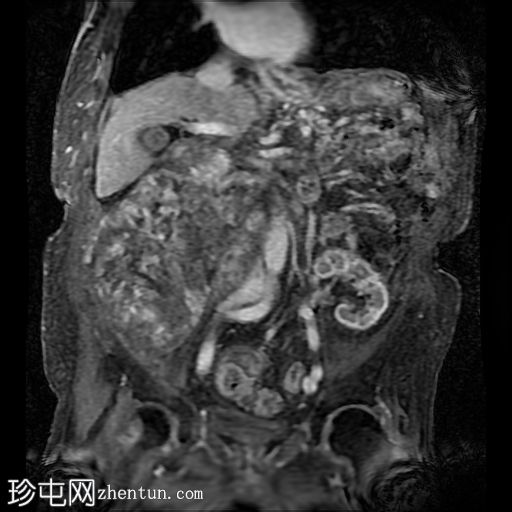

冠状动脉和主动脉瓣膜钙化明显。广泛的腹部动脉粥样硬化。胆结石。双肾萎缩。左髂窝移植肾形态大致正常。

右髂窝移植肾边界不清,呈低密度,周围环绕着一个大的分叶状复杂囊性肿块。